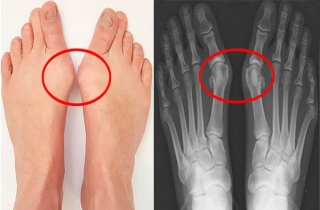

¾öÁö¹ß°¡¶ô ÈÖ´Â ¹«Áö¿Ü¹ÝÁõ, ¼ö¼úÀÌ ´É»ç ¾Æ´Ï´Ù

[µ¥Àϸ®¸Þµð ¹Ú´ëÁø ±âÀÚ] ¾öÁö¹ß°¡¶ôÀÌ ÈÖ¾ú´õ¶óµµ 40µµ ÀÌ»ó °úÇÏÁö ¾Ê°Å³ª ÅëÁõÀÌ ¾øÀ¸¸é ±»ÀÌ ¼ö¼úÇÒ Çʿ䰡 ¾ø´Ù´Â ¿¬±¸°á2020-07-24 10:39:56